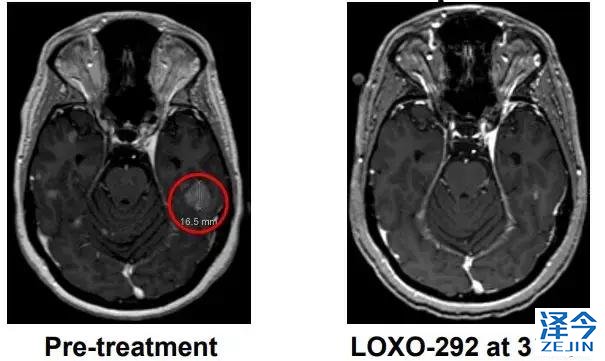

M女士走图无路的情况下接受了基因检测,发现了KIF5B-RET融合,开始接受600 mg BID靶向药 alectinib治疗(PR,7个月),由于脑转移进展增加至900mg BID,后脑转移症状严重,M女士接受了LOXO-292治疗,于是奇迹出现了,治疗两个月后,M女士肺部的病灶明显好转,脑部病灶几乎全部消失!